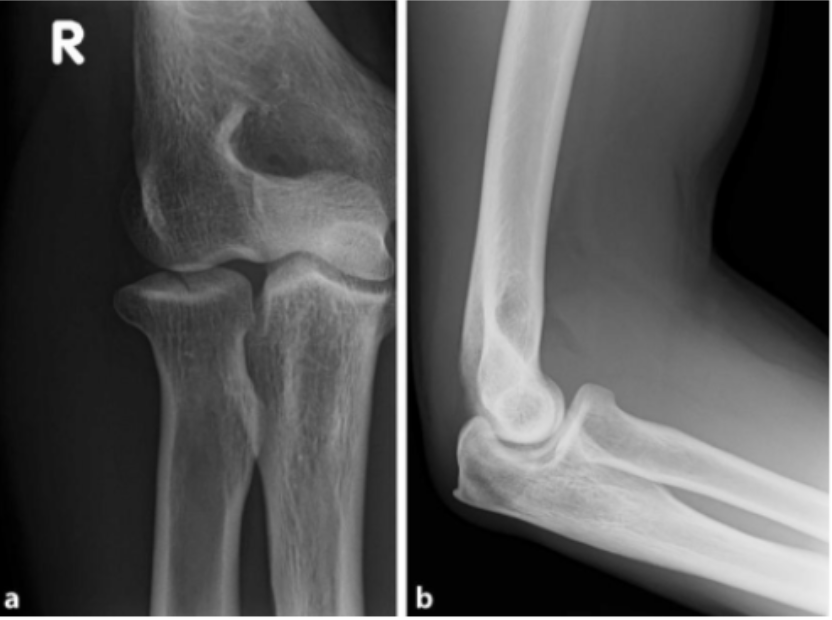

Tipo de fractura en esta rx

Fractura Monteggia anterior (tipo 1)

Mecanismo de lesion de esta fractura

Caída sobre mano extendida con antebrazo en pronación

Fractura de Monteggia posterior (tipo 2)

Trauma directo o lesión de alta energía del antebrazo

CARGA AXIAL CON CODO FLEXIONADO

Tipo de fractura

Fractura de Monteggia tipo 3 (lateral)

Trauma directo al antebrazo o codo, abduccion forzada

Fractura en esta rx

Fractura Monteggia tipo 4

Mecanismo de lesion de la fx

Trauma de alta energía o caída con antebrazo en pronación

PRONACIÓN FORZADA

Tratamiento de fractura de Monteggia

Fijar el cubito con placa (regresa el radio a su lugar), reparacion de ligamentos